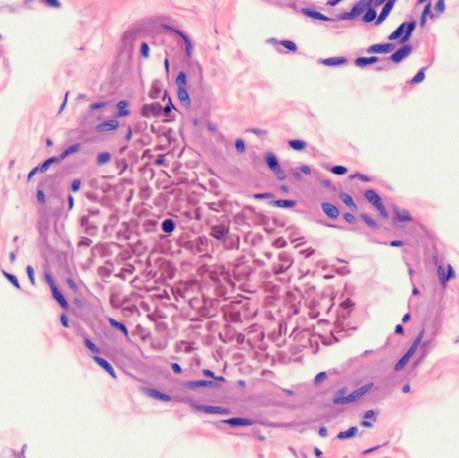

In sections of blood vessels, no matter of artery (Fig. 5-4), vein (Fig. 5-5), or capillary (Fig. 5-6), erythrocytes are found to be biconcave disc shape or dumbbell shape due to cutting. It reveals that the diameter (6-8 μm) of erythrocyte is almost the same as the thickness (7-10 μm) of a paraffin section used for light microscopic observation.